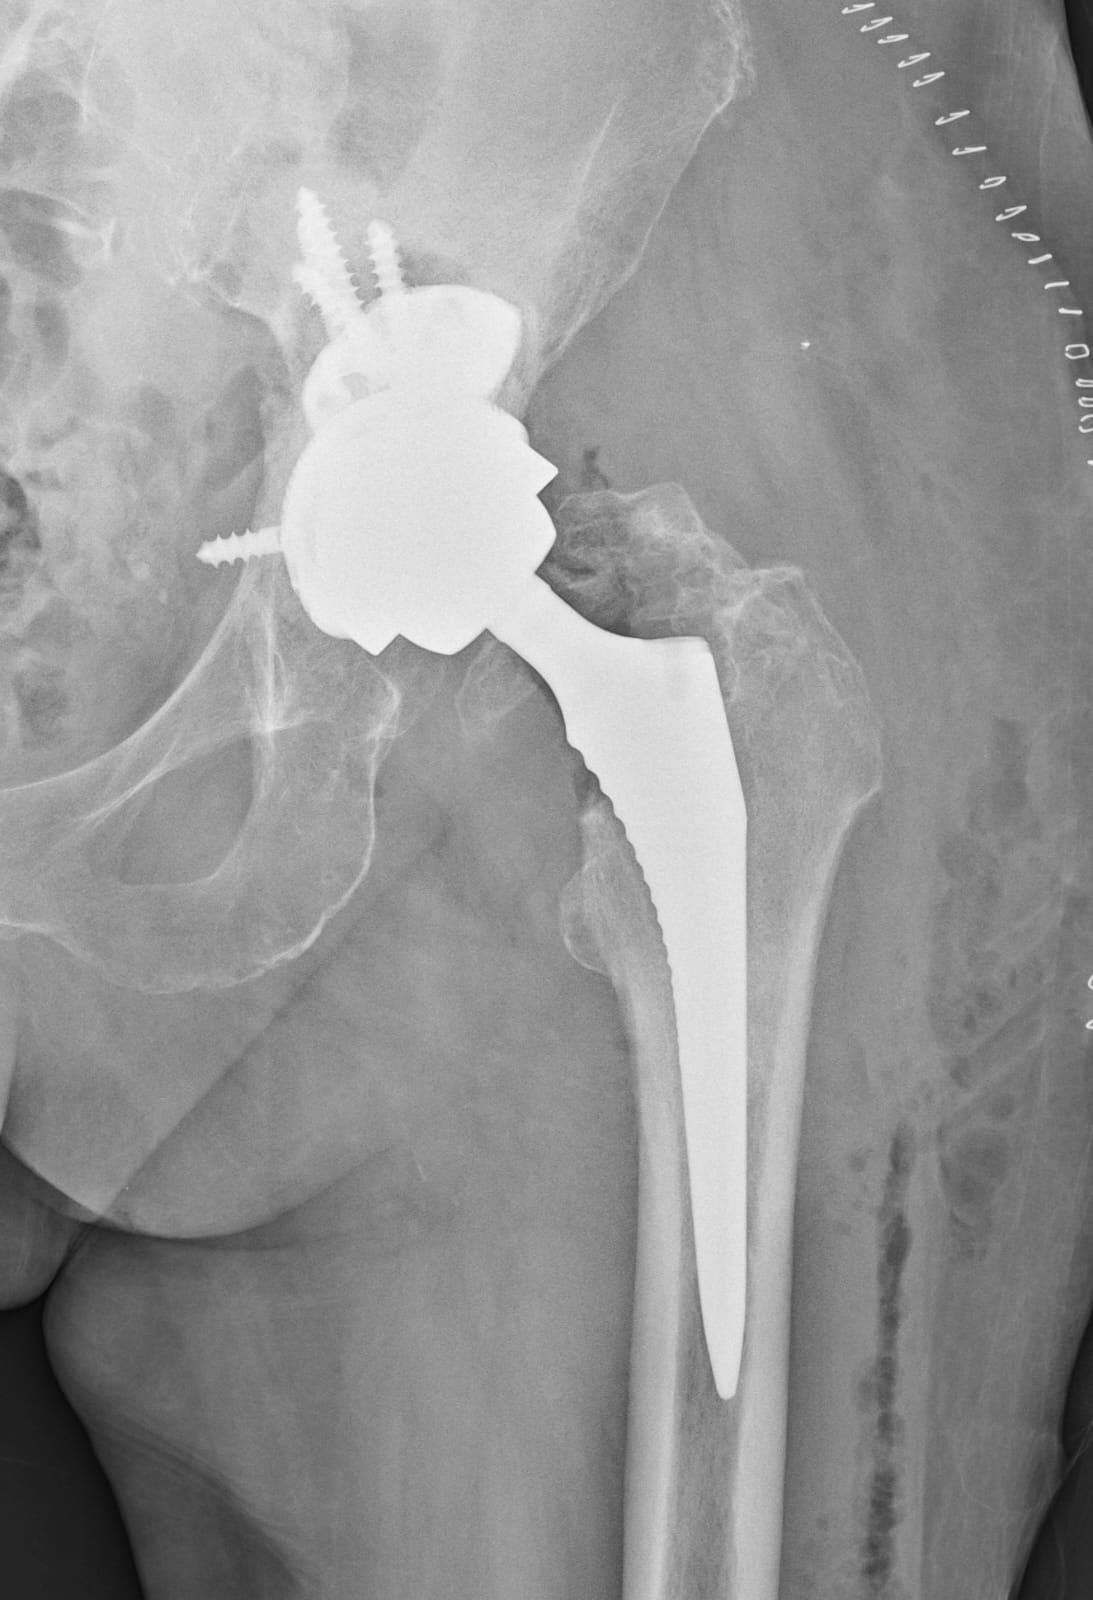

Zdroj: UNB

Kĺb po operácii